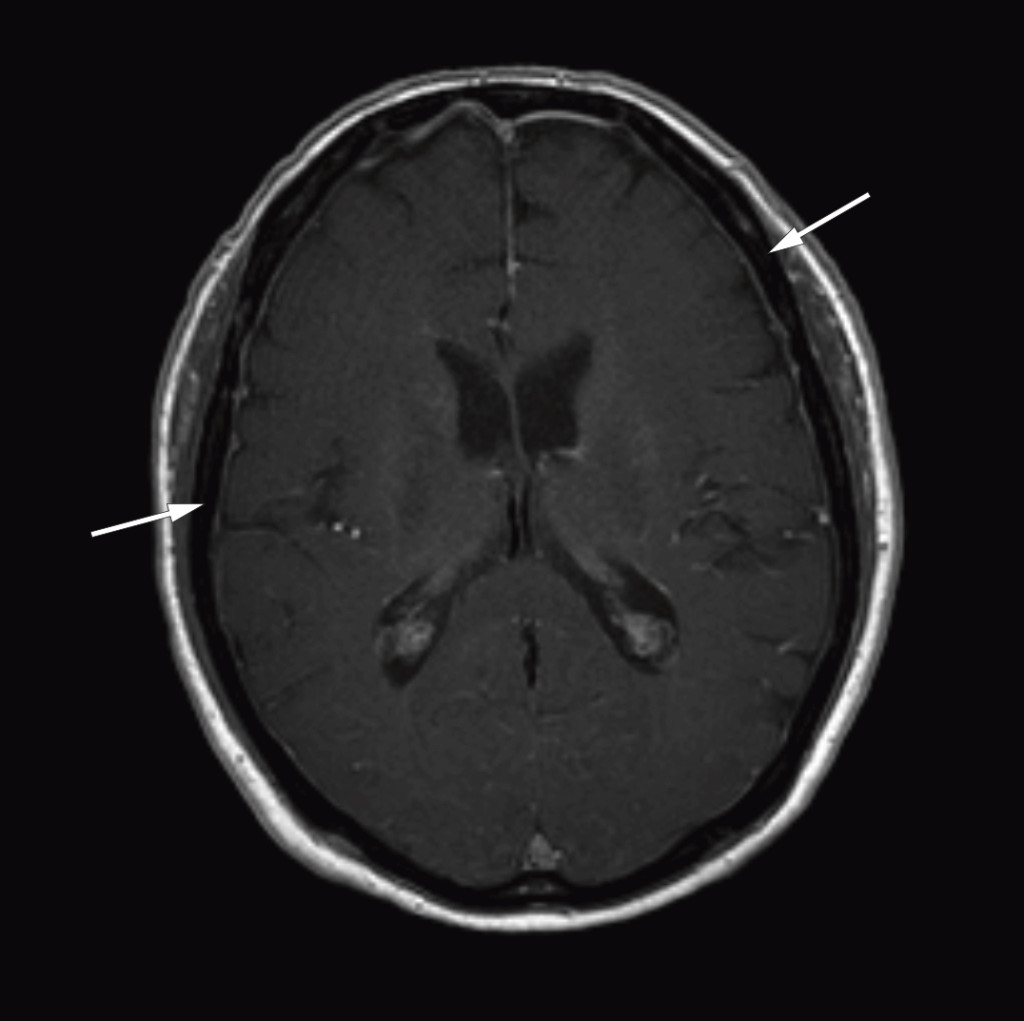

After the diagnosis Bing-Neel syndrome had been made, we studied the MRI images of the cerebrum and lumbosacral column again and found pathologically thickened and contrast-enhanced meninges over both cerebral hemispheres (Fig. 1) and the cerebellum, and wavy, thickened cauda equina roots (Fig. 2). We concluded that the thickened meninges were an expression of diffuse affection of the central nervous system, consistent with Bing-Neel syndrome. The finding of thickened cauda equina roots was also assumed to be related to the syndrome, but this could not be determined with certainty since the changes were limited, and the images had unfortunately been taken without contrast.

Figure 1 Cerebral MRI after injection of contrast medium (axial section) shows thickened and contrast-enhanced meninges over…

Figure 1 Cerebral MRI after injection of contrast medium (axial section) shows thickened and contrast-enhanced meninges over both cerebral hemispheres.